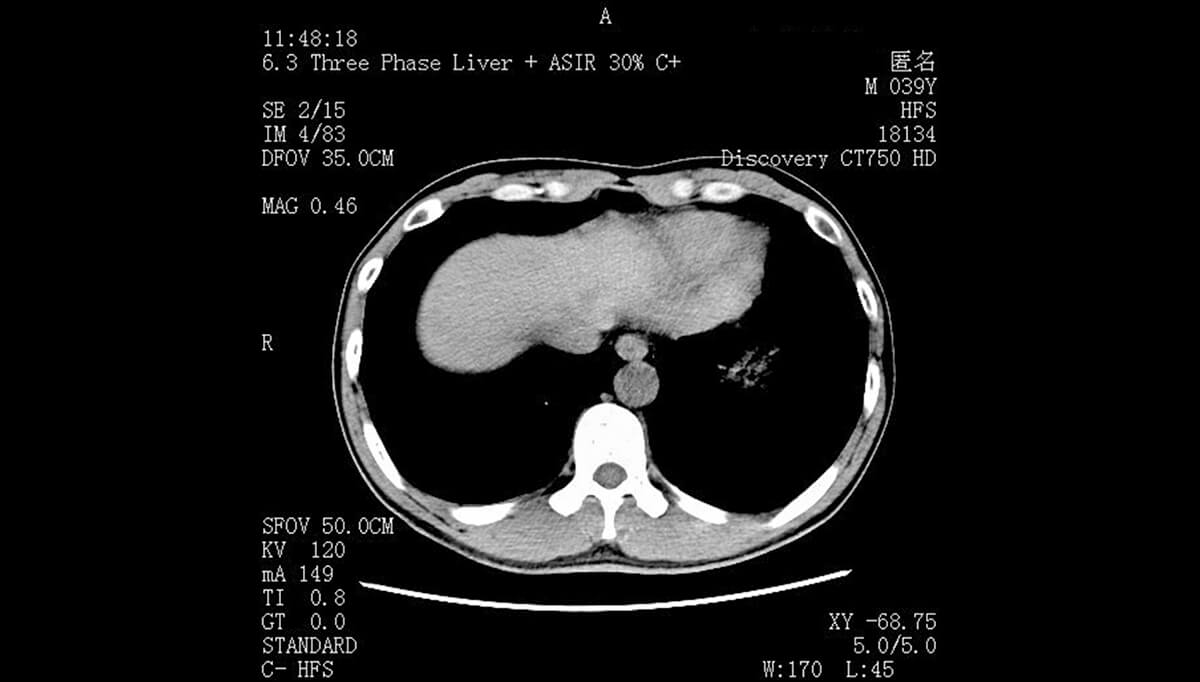

在诊疗效率提升方面,睿显云胶片展现出显著优势。患者检查完成后,无需等待胶片打印,医生可通过移动终端即时获取完整 DICOM 影像,大幅缩短就诊流程。上线该系统后,患者扫码即可查看高清影像,彻底解决了传统胶片等待时间长、携带不便的痛点。针对基层医生阅片需求,该医疗影像软件支持影像放大、窗宽窗位调整等功能,帮助医生更精准地观察病灶,降低误诊率。